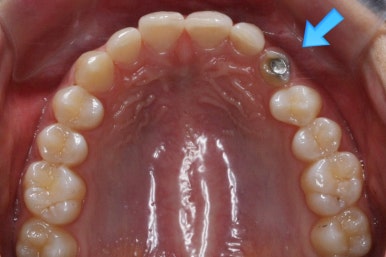

부산매복치아교정 키다리아저씨치과에 처음 내원하셨을 때의 X-ray 사진입니다.

좌측 사진은 파노라마라고 하는 전체가 다 나오는 사진이고, 우측 사진은 해당 부위만 확대해서 찍은 사진입니다.

화살표 표시가 바로 송곳니가 매복이 되어있는 모습입니다. 수직하게 내려오지 못하고 무시무시하게 가로로 누워있는 모습입니다. 입 안에서도 전혀 관찰되지 않고 오로지 뼈속에 있는 상태입니다.

이럴 경우 평면적인 2D X-ray로 정확한 판단이 되지 않습니다.

3차원 CT를 통해 더 정확한 위치를 파악할 필요가 있습니다.